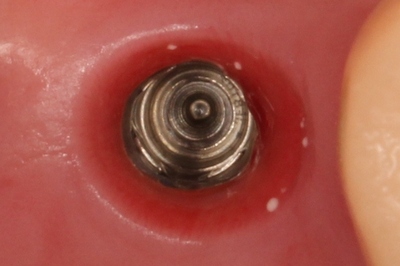

N・Sさんの右上のインプラント治療がアバットメントのスキャニングを迎えました。

アバットメントのスキャニングのため、ヒーリングキャップを取り外しました。

アップです。

白い粒子はハミガキ剤に含まれる研磨粒子と考えられます。

天然歯においては歯肉溝がインプラントより浅いため、問題ないものと思われますが

インプラントの場合は歯肉溝に相当する部分が深いため、研磨粒子の残存・歯肉への迷入が起こりやすいようです。

研磨粒子が残っていても、すぐさまそれが問題となるとは限りませんが、本来存在して欲しくないものですので注意が必要と考えます。